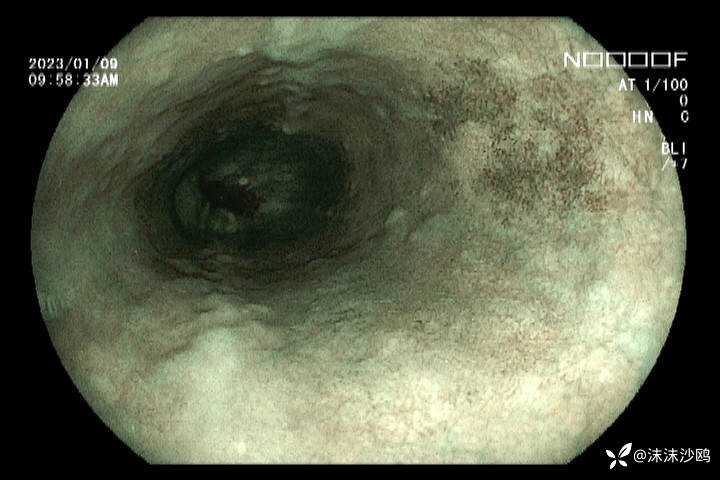

21年内镜

22年第二次是在上级医院检查并取了活检,没有大问题(我没见到病检结果。